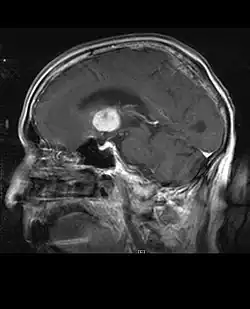

La tomodensitométrie (TDM) et L'imagerie par résonance magnétique (IRM) peuvent détecter efficacement une néoplasie dans le cerveau. L'IRM est plus sensible que la TDM pour identifier les lésions, mais présente des contre- indications pour les patients porteurs de stimulateurs cardiaques, de prothèses incompatibles, de clips métalliques et contre-indications. La TDM reste la méthode de choix pour détecter les calcifications au sein des lésions ou les érosions osseuses de la calotte ou de base du crâne. L'utilisation d' agents de contraste, iodés dans le cas du scanner et paramagnétiques (gadolinium) dans le cas de l'IRM, permet l'acquisition d'informations sur la vascularisation et l'intégrité de la barrière hémato-encéphalique, une meilleure définition de la tumeur tumorale par rapport à l' œdème environnant et à la génération d' hypothèses sur le degré de malignité. L'examen radiologique permet également d'évaluer les effets mécaniques et les modifications importantes des structures cérébrales résultant de la tumeur, telles que l' hydrocéphalie et les hernies, dont les effets peuvent être fatals. Enfin, en préparation à la chirurgie, ce diagnostic peut être utilisé pour déterminer la localisation de la lésion ou l'infiltration de la tumeur dans des zones vitales du cerveau. À cette fin, l'IRM est plus efficace que la tomodensitométrie car elle peut fournir des images en trois dimensions.

Sur-L'IRM montre une tumeur intracrânienne comme une lésion massive qui peut devenir plus luminescente après utilisation du produit de contraste. Cependant, il y a toujours une anomalie de signal dans -L'imagerie par résonance magnétique, qui indique la présence d'une néoplasie ou d'un œdème vasogénique. Habituellement, une luminescence accrue (amélioration du contraste) indique une tumeur d'un grade supérieur de malignité. Un anneau de contraste est caractéristique du glioblastome, avec la partie luminescente correspondant à la partie vitale de la tumeur maligne, et la plus foncée - zone hypointense correspondant à une nécrose tissulaire.